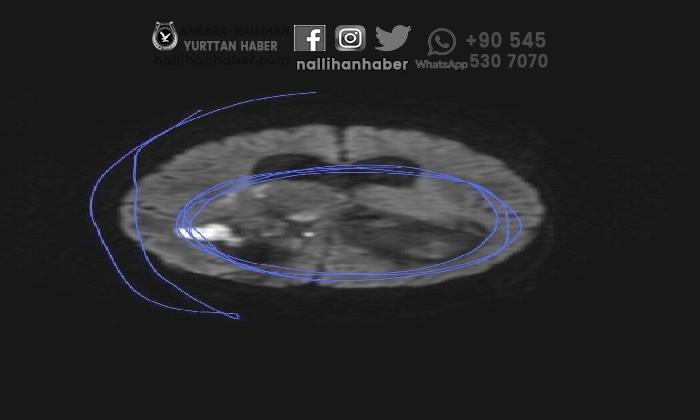

Yapılan tetkikler sonucu Arif Kahraman’a yetişkinlerde rastlanılan ve 100 bin şahıstan 10 şahısta ender görülen ‘Glioblastoma’ makûs huylu tümör teşhisi konuldu. Hekimler aileye, ender görülen bir hastalık olduğunu ve tümörün 3 yaşındaki Arif Kahraman’ın beyninin tamamını kapladığını söyledi. Oğlu Arif Kahraman’ın 10 ay hastanede hayat çabası verdiğini belirten Büşra Kahraman, yetkililerden yardım istiyor.

Hastanede çocuğumun tomografi ve MR’ı çekildi. Çocuklarda az görülen 4’üncü evre yetişkin Glioblastoma tümörü olduğu teşhisi konuldu.

Patoloji kısmından çocuğumun başından kesim aldılar. Tümör hudut sisteminde olduğu için omurilik suyunun akmadığı tespiti yapıldı.

Haziran ayında tümörün büyümesi nedeniyle şuuru kapandı ve ağır bakıma kaldırıldı. Tümör beyninin büyüklüğü kadarmış. Oğlum 10 aydır hayat gayreti veriyor.